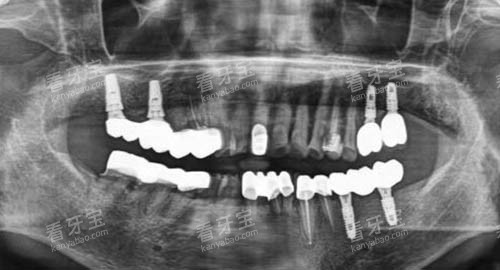

为了给患者提供更更准一些、较高的效率的治疗服务,十堰品冠口腔门诊部引进了一系列较高的医疗设备。

如智能化口腔全景机,能够清晰地拍摄口腔的全景图像,帮助医生齐全了解患者的口腔状况;口腔种植导航系统,在牙齿种植手术中可以正确地定位种植体的位置和方向,提高手术的成功几率;牙齿美白冷光仪,采用较高的冷光技术,能够快速、可靠地实现牙齿美白结果。

这些较高设备的应用,不仅提高了诊断的较准性和治疗的结果,还大大缩短了患者的治疗时间。